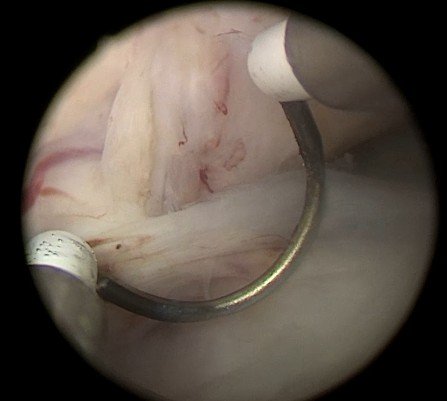

Herrmann Electrode